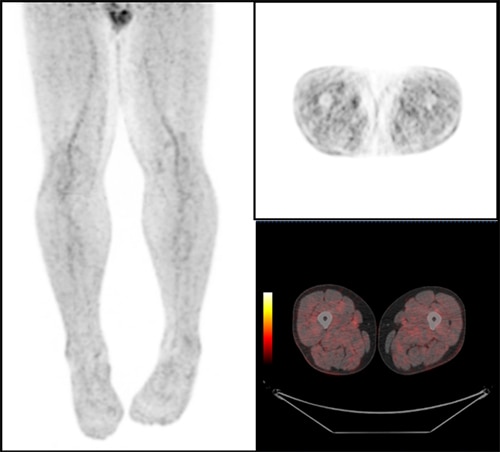

臨床に用いる収集条件は、核医学会が定める「18F-FDGを用いた全身PET撮像のためのファントム試験手順書」に準じたNEMA IEC Bodyファントムによる物理評価と、実際に診断するPET核医学専門医師の視覚評価(図4、図5)により決定しました。運用開始当初は、1bed 120秒撮像、Q.Clear β400で再構成を行っていましたが、収集時間をもう少し短く出来るのではないかと考え再検討し1bed 90秒撮像、Q.Clear β500の再構成としました。Precision DL(PDL)は、元の画像の特徴を大きく変えずにノイズが除去できるMediumを使用しています。

図4. 撮像時間90s

図5. 撮像時間120s